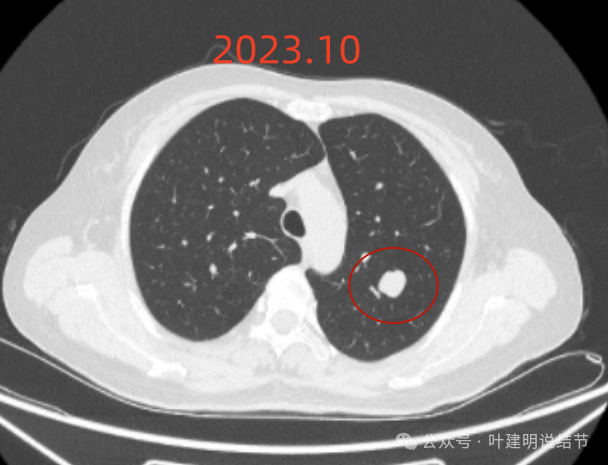

先看不同时间段的病灶影像:

2019年5月时左上叶实性结节,边缘很光滑,没有毛刺或血管征,影像上看像良性的。

2019年10月,变化不大,但这个层面看略显得有膨胀感。

2024年10月,病灶较2019年时明显显得大了一些,挨着邻近血管了。

2023年12月,与血管已经贴着了。整体较最早时大了不少。

左上叶这个病灶看影像感觉边缘比较光滑,内部密度较为均匀,似乎是良性的。但我们如果将其2019年到2023年底的最大层面的影像放在一起对比,病灶是逐渐有增大的。2023年12月的肿块出现浅分叶、整体感觉鼓鼓的,原来病灶与旁边血管是有距离的,但最近这次的已经紧贴着了。但在纵隔窗看,病灶并无钙化或内部坏死密度,说明不太符合肉芽肿性炎或慢性炎性病灶。我觉得要十分倾向恶性肿瘤!低度恶性或交界性肿瘤可能性大。之前我碰到过随访10年的边缘光滑的实性病灶,从3厘米增大到8厘米多,术后是神经内分泌肿瘤的。我的想法还是要考虑切了,术前也可再复查下PET-CT,看看代谢是否活跃。但其实即使代谢轻度增高,也是放着不放心的。若是无代谢的,当然则与恶性不太符合(这种可能性是小的,无代谢不可能又增大)。这个位置穿刺可试试,但有点深,是否可行要与穿刺实施的科室医生沟通看看,若穿刺恶性仍得开刀,穿刺没见到癌细胞,但随访增大仍不放心。个人其实不是特别推荐穿刺。意见供参考!